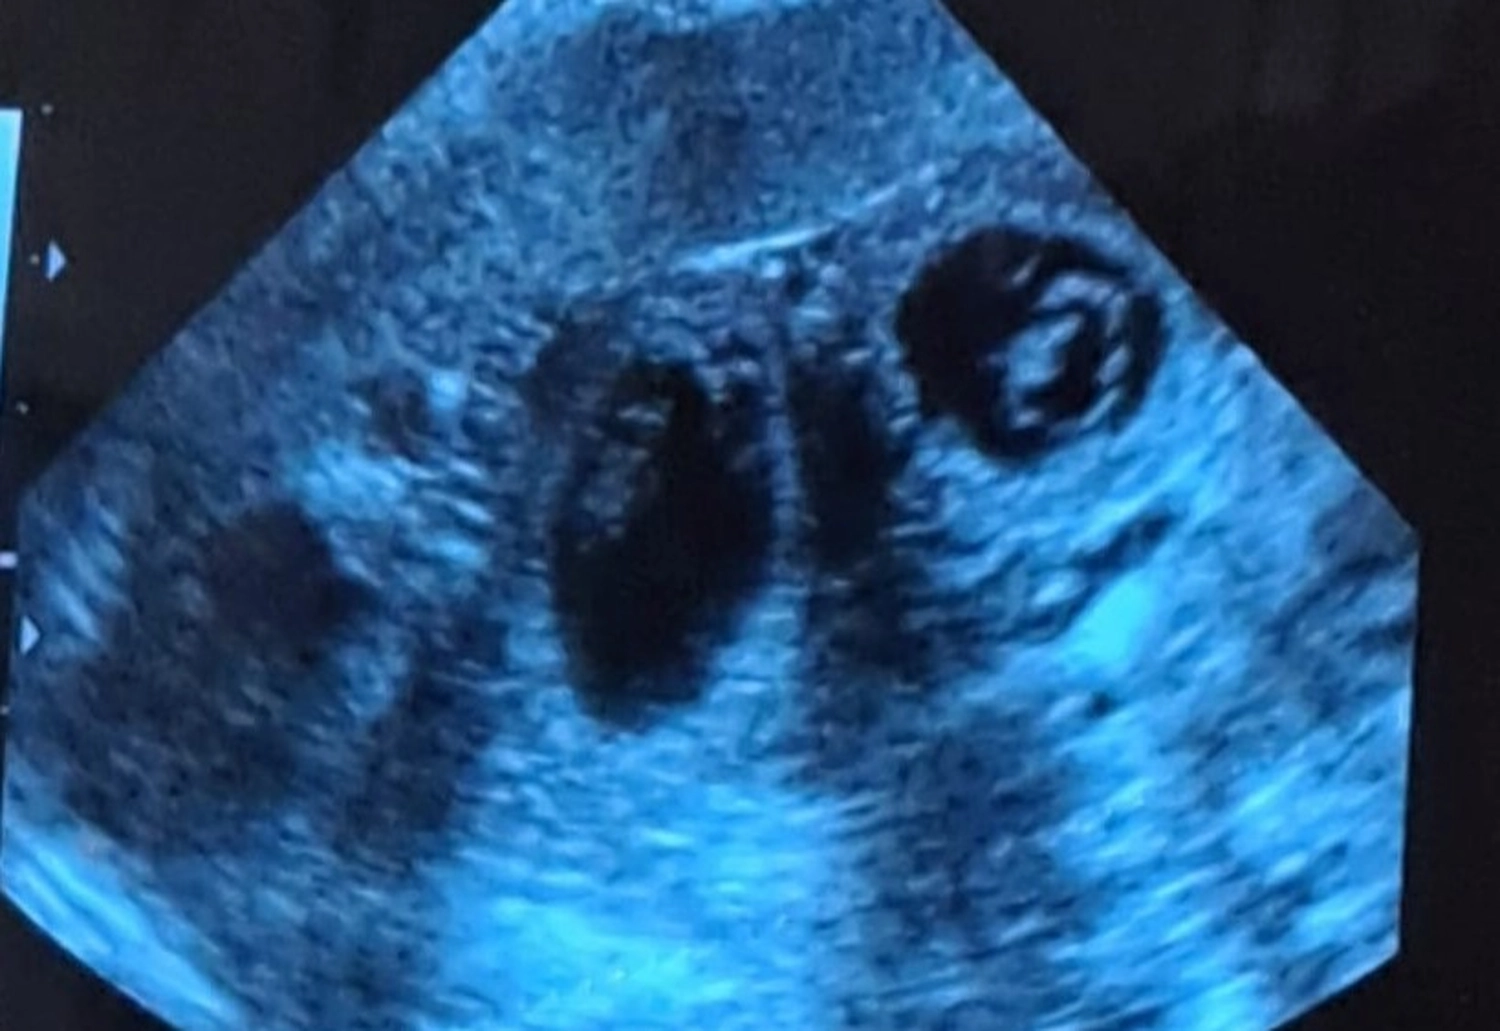

Heute wurde eine Ultraschalluntersuchung von Josy gemacht, um zu sehen ob sie aufgenommen hat. Lt. Tierarzt ist Josy tragend, er meinte, "es sind mehrere Welpen drin".

Jetzt heißt es hoffen, dass alles gut geht.